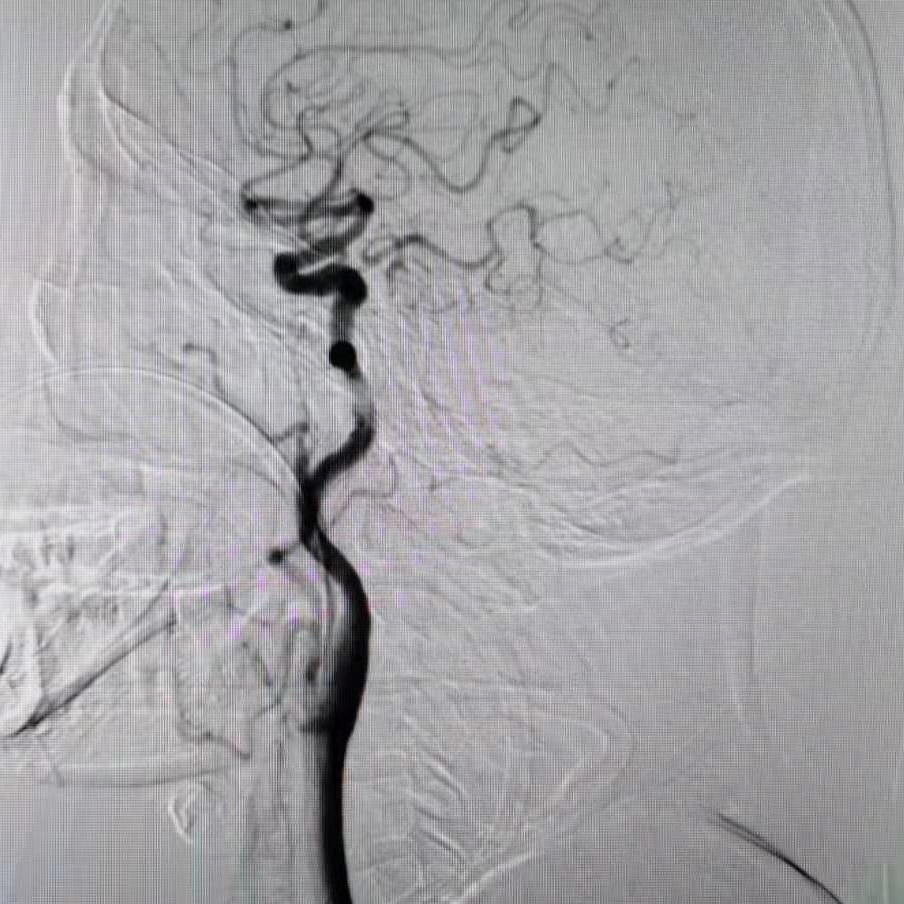

全脑血管造影提示右侧椎动脉颅内段闭塞,左侧椎动脉颅外段走形迂曲,基底动脉近端闭塞。

颈动脉造影示后交通开放。

5F 115cm远端通路导管超选至左侧椎动脉V2段,选取术中工作角度造影。

扩张后造影,提示恢复正向血流,残余狭窄50%左右。发现加奇SacSpeed® 2.5mm×9mm颅内球囊扩张部位存在双腔征,考虑血管夹层,给予替罗非班8ml/h持续泵入。

通过长交换技术,将XT-27定位在右侧大脑后动脉P2段,将Neuroform颅内支架3.5×15mm,定位在基底动脉狭窄处。

释放支架。